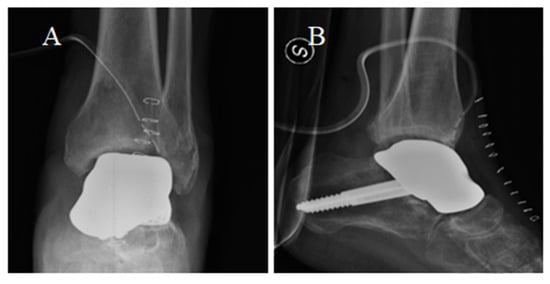

2.2.3. Secondary Osteoarthritis and Revision to Total Ankle Prosthesis

During the second year of follow-up, the patient experienced a worsening, up to the impossibility of walking without pain. He soon started complaining of painful plantar flexion and morning stiffness. A ROM limitation (ROM = 20°) was observed at the control visit. Two years after surgery, antero-posterior and latero-lateral ankle radiographs suggested a secondary osteoarthritis with articular space narrowing, implying the indication for a prosthesis revision (Figure 9). Either arthrodesis or tibial resurfacing were proposed as management options. In this case, the patient expressed the desire to maintain ankle function: A conversion to total ankle arthroplasty with TTR was performed. The tibial prosthesis consisted of a tibial trabecular titanium (Ti6Al4V) component and 6 mm-thick, high-density polyethylene (Figure 9). The lengthening of the Achilles tendon was performed using a percutaneous technique.

Figure 9.

Two-year post-surgery X-ray of the implant from antero-posterior (A) and latero-lateral (B) projections. Articular space narrowing and osteophyte formation (compared with Figure 7) can be observed (A,B). The total talar replacement after revision surgery from antero-posterior (C) and latero-lateral (D) projections. Image courtesy of Dr. Paola Verde Aerospace Medicine Department, Aerospace Test Division, Pratica di Mare, Rome, Italy.